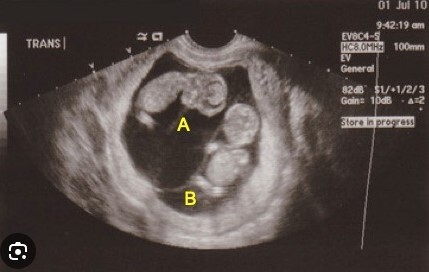

Q

A

Think twin-twin transfusion syndrome

Note: Twin A has polyhrdramnios and twin B has oligohydramnios (AKA TOPS/Twin Oligohydramnios Polyhydramnios Sequence).